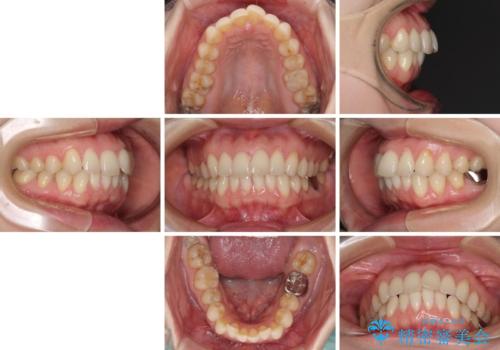

出産をしながら歯列を整える インビザラインによる矯正治療

- 1年2ヶ月

- 上下の前歯のデコボコを気にして来院された患者様です。

妊娠中であり、途中通院が難しくなる可能性があることから、インビザラインによる矯正治療を行うこととしました。

上下顎歯列全体の後方移動とIPR(歯と歯の間を削る)によってデコボコが解消するように設計しました。